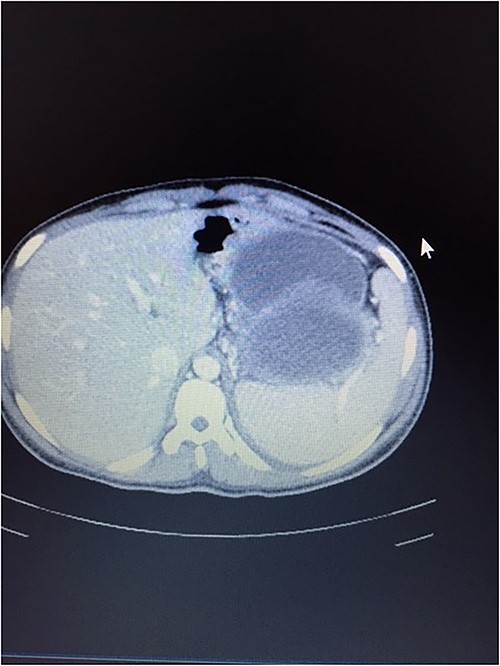

A 14-year-old female with no relevant past medical history presented with a 2-week history of right upper quadrant abdominal swelling. She gave no history of trauma, pain, fever, jaundice, alteration in bowel habits, early satiety, bloating, or anorexia. On physical examination, she appeared healthy. Her vital signs were normal, and she was anicteric. The rest of her exam was normal except for a right upper quadrant fullness and a palpable liver edge 6 cm below the right costal margin. An abdominal ultrasound was interpreted as a right lobe liver mass. A fine needle aspirate revealed necrotic tissue with no hepatocytes seen. A thoraco-abdominal CT scan revealed an enhancing, centrally necrotic retroperitoneal mass of 9 × 12 cm compressing the duodenum, portal vein, and inferior vena cava. Mild adjacent free fluid was noted. There was no evidence of metastatic disease (Fig. 1). All routine blood tests including complete blood count, chemistries (amylase and lipase inclusive) and coagulation studies were normal. A gastrointestinal stromal tumor was suspected.

A contrast-enhanced CT scans of the abdomen showing a large, well-defined, and heterogeneous tumor.